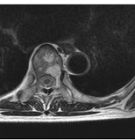

5、 MRI 診斷:

MRI 對含血管的病灶敏感性較好,肝血管瘤血管腔內含有緩慢的血液流動, 其T1及T2弛豫時間較實體瘤為長。本法的檢出率較高,但價格亦較高。總之診斷肝血管瘤的超聲及CT最為方便,而血池掃描與肝動脈造影為確診手段。